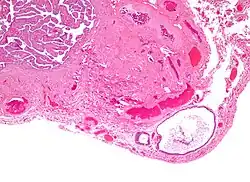

Histology of a Walthard cell rest in a fallopian tube with typical features (H&E stain):

- Cyst (may also be solid nest) of transitional type epithelium.

- Eosinophilic luminal secretions.

Micrograph of a cystic Walthard cell rest (lower right of image) within the connective tissue of a fallopian tube (tubal epithelium – upper left of image). H&E stain.